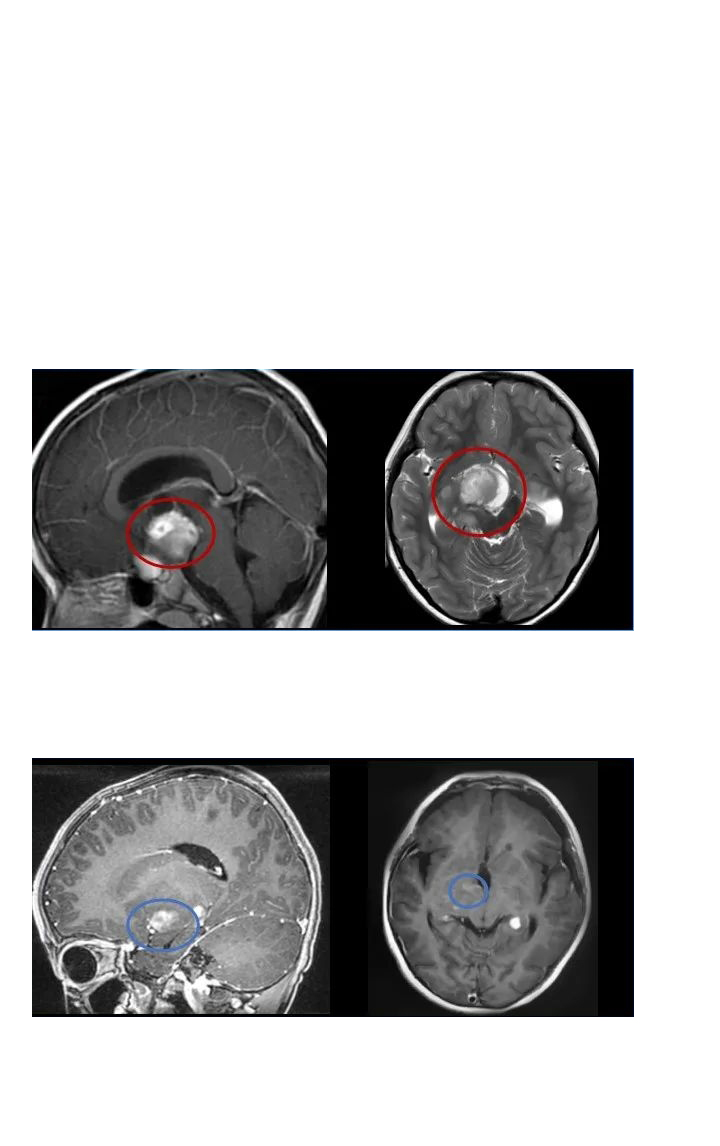

毛細胞型星形細胞瘤是一種預(yù)后較好的低級別膠質(zhì)瘤,不管發(fā)病位置在哪里,手術(shù)全切基本可達到不復(fù)發(fā)的更好效果。在治療中,一次手術(shù)尤為重要,應(yīng)在不損傷患者正常腦組織和功...

INC國際教授毛細胞型星形細胞瘤疑難手術(shù)案例

毛細胞型星形細胞瘤是一種預(yù)后較好的低級別膠質(zhì)瘤,不管發(fā)病位置在哪里,手術(shù)全切基本可達到不復(fù)發(fā)的更好效果。在治療中,一次手術(shù)尤為重要,應(yīng)在不損傷患者正常腦組織和功能神經(jīng)的前提下切除腫瘤,避免復(fù)發(fā)和后遺癥,更大水平好轉(zhuǎn)患者術(shù)后生存質(zhì)量。